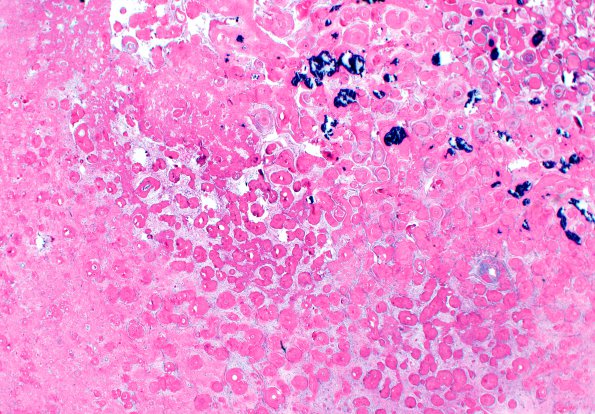

Washington University Experience | MISCELLANEOUS | Amyloidoma | 2A2 Amyloidoma (Case 2) H&E 10

2A2,3 However, higher magnifications show an unusual collection of thick, apparently unstructured, material surrounding a central vessel in many cases (H&E)